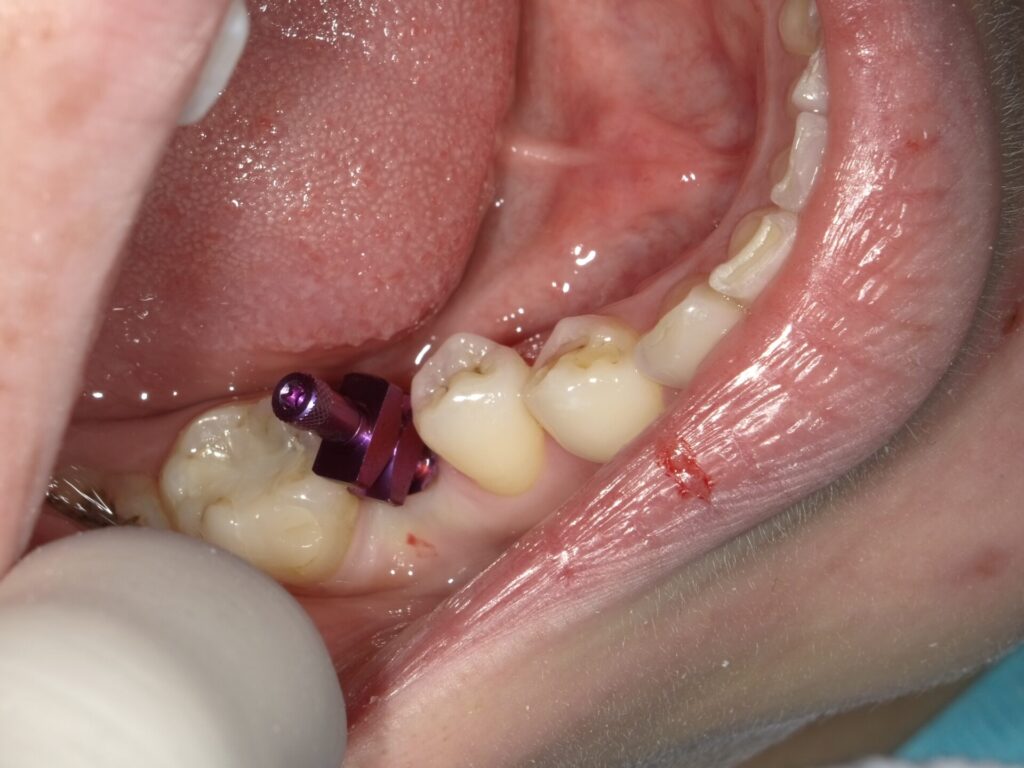

画像の紫の棒がインプレッションポストといいこの上に

型取りの材料を入れます。